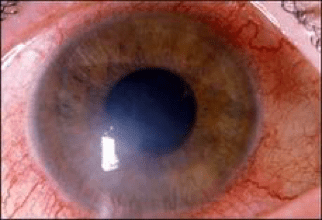

Είναι γεγονός ότι μπορούμε να μειώσουμε τη διείσδυση της ηλιακής ακτινοβολίας μέσα στα μάτια μας με διάφορους τρόπους, όπως το αντανακλαστικό κλείσιμο της κόρης στο έντονο φως ή το εκούσιο κλείσιμο των βλεφάρων. Εντούτοις, αυτό μπορεί να συμβεί σε συνθήκες έντονου ορατού φωτός. Οι μηχανισμοί αυτοί δεν μπορούν να ενεργοποιηθούν από έκθεση σε υπεριώδη ακτινοβολία, η οποία μπορεί να εξακολουθεί να είναι σε υψηλά επίπεδα, ακόμη και σε ημέρες που υπάρχει συννεφιά. Καταλαβαίνουμε επομένως ότι αυτές οι "φυσικές άμυνες" έναντι της υπεριώδους ακτινοβολίας είναι περιορισμένες.